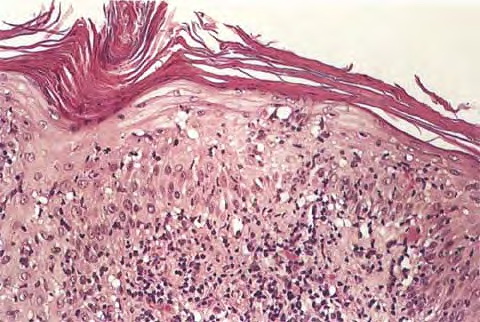

Pilar cyst = كيسة الشعر Pilar Cyst Pilar or trichilemmal cysts are clinically indistinguishable from epidermal cysts but differ from them in frequency and distribution. They are less common than epidermal cysts, constituting only about 25% of the combined material; about 90% occur on the scalp . Pilar cysts often show an autosomal dominant inheritance […]